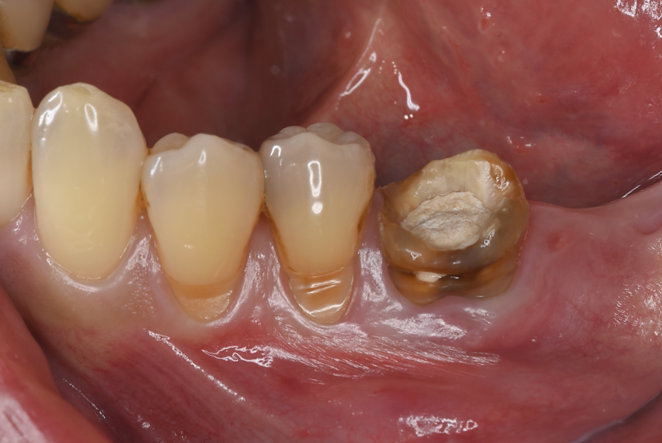

| 患者様データ | 40代 女性 |

| 来院時の主訴 | 「左側奥歯で噛むと痛い。」 |

| 医院の診断 | 歯根破折、慢性根尖性歯周炎 |